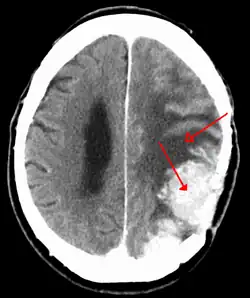

![]() | |

An MRI of the brain, demonstrating the appearance of a meningioma | |

Meningiomas are visualized readily with contrast CT, MRI with gadolinium,[23] and arteriography, all attributed to the fact that meningiomas are extra-axial and vascularized. CSF protein levels are usually found to be elevated when lumbar puncture is used to obtain spinal fluid. On T1-weighted contrast-enhanced MRI, they may show a typical dural tail sign absent in some rare forms of meningiomas.[18]